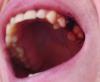

Andrew Oldman Опубликовано 1 марта, 2013 Поделиться Опубликовано 1 марта, 2013 Извините если нужно было открывать эту тему в разделе хирургии. Посоветуйте пожалуйста, что делать.. Ситуация следующая:3 дня назад мне удалили верхний 5 зуб (там был один корень). Операция прошла с некоторыми трудностями (трудно было ухватиться), но все же без чрезвычайных сложностей. На сакмо удаление ушло минут 15-20. Врач настоятельно рекомендовал не полоскать рот в течении суток, таблеток не выписывал и сказал если будет болеть, выпить обезбаливающее... После того как я убрал тампон (мин 40), десна еще немного покровила и через пару часов прошла. В первые сутки была терпимая боль, посему таблетки не принимал, потом и вовсе прошло. Правда была температура до 38 и пульсирующая головная боль (у меня ОЧЕНЬ редко болит голова). Я сослался на простуду, так как на работе все поболели перед этим. Выпил колдфлю, много чая (теплого, гарячее стоматолог запретил есть) и все прошло.. А сегодня ночью встал в туалет и обнаружил что из десны где было удаление вылез сгусток крови и мне кажется, что подтекала и свежая (но могу ошибаться). Сутра когда встал постоянно сплевывал кровавой слюной, так как она (слюна) набиралась, а глотать не хотелось. Через час-полтора крови в слюне значительно уменьшелось, но сгусток висит между соседними зубами. Звонил в стоматологию, записался на 15:00. Но девочка ничего не посоветовала так как она не врач, а врач будет с 15:00.. Боюсь завтракать, чистить зубы, чтоб не сорвать его совсем и не занести заразу в лунку. Помогите советом пожалуйста... Сейчас ничего не болит, температуры нет, чуствую себя хорошо. Правда кушать хочу, а страшно... Извините фото с телефона, как мог сфоткал.. Ссылка на комментарий